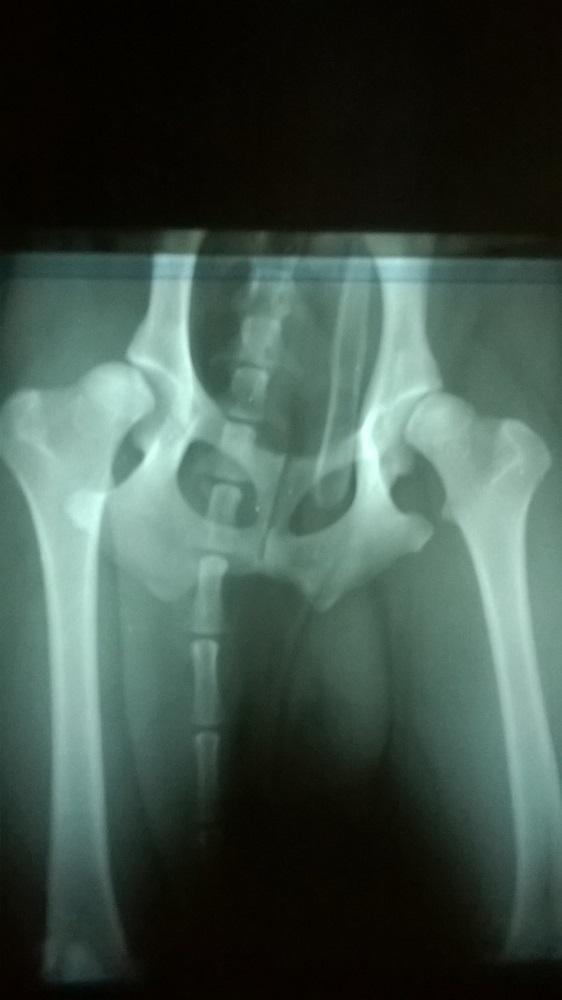

11. Witam. Mam zwykłego kundelka, ma rok i 2 miesiące. Miesiąc temu stwierdzono u niego dysplazję. Miał przeprowadzane dwa zabiegi nie pamiętam konkretnie jak to się nazywało ale wstrzykiwano mu coś do stawów. Niestety brak efektów. Wczoraj byłam u innego specjalisty gdzie otrzymałam większą pomoc lecz decyzja należy do mnie. Doktor zaproponował mojemu pieksowi 3 opcję. Odnerwienie, Daroplastyke oraz Dekapitację. Zatrzymaliśmy się na daroplastyce i dekapitacji. Kompletnie nie wiem na co się zdecydować. Chciała bym dla niego jak najlepiej więc nie wiem co mam zrobić. Nie jestem weterynarzem i kompletnie nie znam się na tym więc tym bardziej ciężej jest mi podjąć taką decyzję. Boję się, że po zrobieniu daroplastyki mojemu psiakowi się nie polepszy i kolejne pieniądze i zdrowie psa pójdzie na marne. Natomiast jeżeli chodzi o dekapitację to boję się, że jest to zbyt ciężki zabieg jak na taką dysplazję. Postaram się załączyć zdjęcie RTG. Błagam pomóżcie nie wiem co mam zrobić. :-( [attachment=3163:11214.attach]

5. Dziękuję za wszystkie rady naprawdę pomagacie... Ktoś może się orietuje ile taka resekcja może kosztowć ? Wiem, że każdy wet inaczej ale mniej więcej ? I co jeśli ja bym musiała zrobić obu łapek. Zdjęcie wykazuje, że prawa jest w gorszym stanie ale w rzeczywistości to tą lewą ciągnie za sobą. Poza tym robią się powoli zmiany zwyrodnieniowe. Czy można zrobić resekcję obu łapek na raz?

1. Niee nic mi nie mówił ;p Chyba zachwaliłam mojego Elmo jak napisałam, że na razie ok. Na następny dzień znowu to samo. Pies nie biegał ani nic a chodzić znowu nie mógł. Z każdym podniesieniem się był pisk. Prześwietlenie wykazuje, że gorzej wygląda prawa noga a bardziej go boli lewa. Od jutra zaczynamy pływanie bo dzisiaj przyszedł kapok. Jakoś za 2 tyg umawiamy się na operację. Nie wiem czy tu już jakikolwiek lek tu pomoże.. ;c